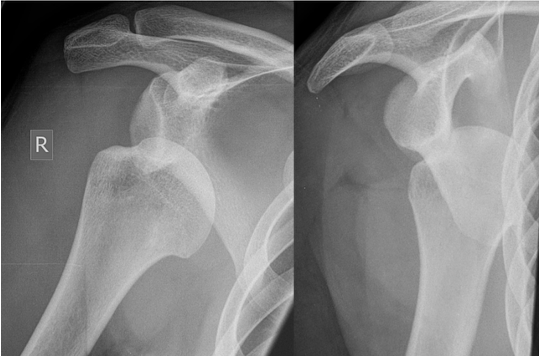

Les pathologies liées à l’épaule

Selon la pathologie affectant l'articulation de l'épaule, les options thérapeutiques, qu'elles soient médicales ou chirurgicales, seront abordées lors de la consultation, en tenant compte de vos examens médicaux et de vos attentes fonctionnelles.